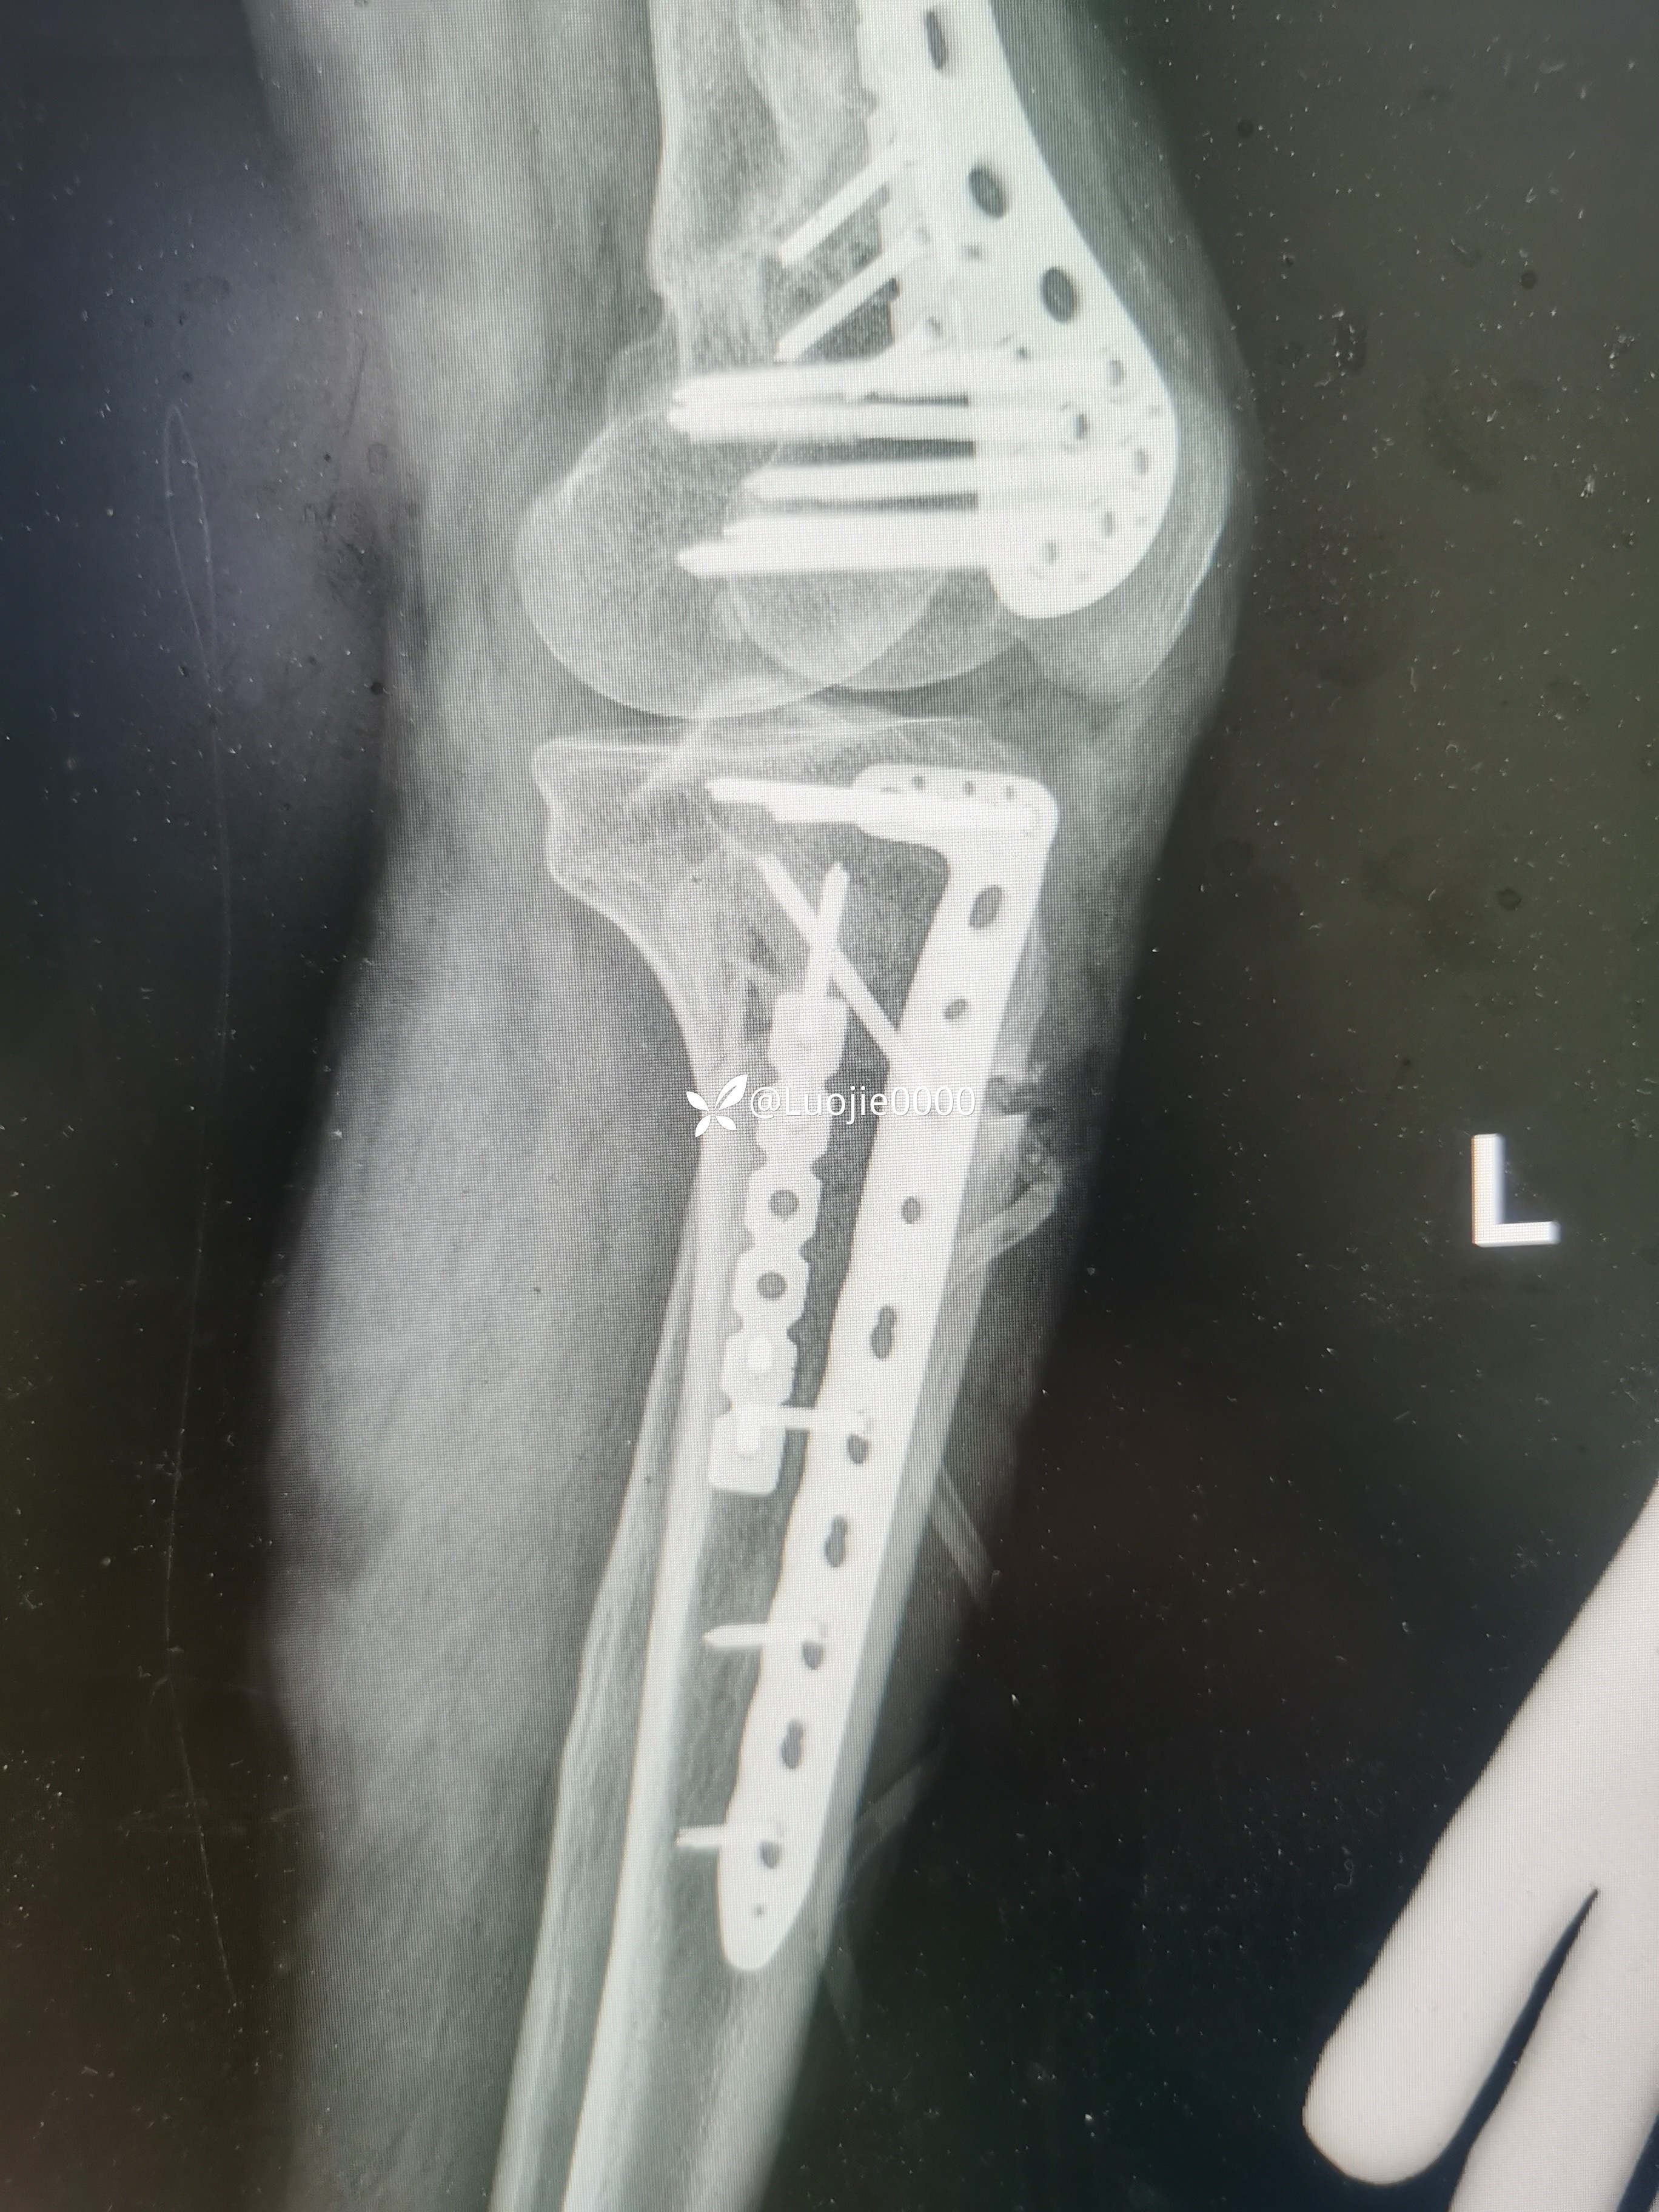

辅助检查:DR及CT提示:左胫骨近端及腓骨头骨折。

影像资料如下:

照书做没成功

切开复的位